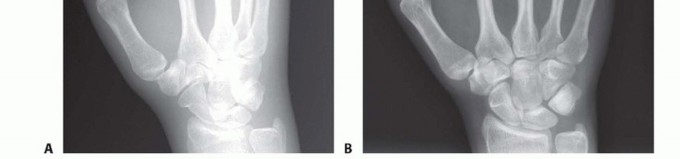

Standard radiographic imaging forms the cornerstone of diagnostic evaluation, requiring, at minimum, a dedicated posteroanterior (PA), a true lateral, and a pronated oblique view of the injured hand. The PA view is excellent for assessing coronal plane angulation and transverse displacement, though it notoriously underestimates sagittal plane deformity. The true lateral view is critical for quantifying apex-dorsal angulation, though overlapping metacarpal shadows can complicate interpretation. The pronated oblique view often provides the clearest visualization of the fracture profile and the degree of comminution.

When standard radiographs are equivocal, or when dealing with complex intra-articular fractures and suspected CMC fracture-dislocations, advanced cross-sectional imaging is mandatory. High-resolution Computed Tomography (CT) with 3D reconstructions provides unparalleled detail of articular step-offs, occult comminution, and the precise spatial orientation of fracture fragments. This information is invaluable for determining the feasibility of lag screw fixation versus the necessity of bridge plating. Furthermore, obtaining radiographs of the uninjured, contralateral hand serves as a vital anatomical template, allowing the surgeon to accurately gauge the patient's native metacarpal length and intrinsic diaphyseal curvature.

Clinical & Radiographic Imaging Archive